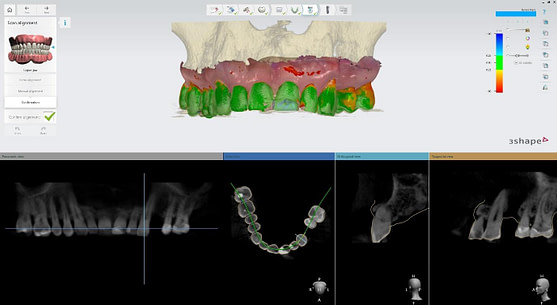

By combining data from 3shape TRIOS intraoral scans, CBCT imaging, and other diagnostic sources, TRIOS enables practitioners to visualize and create treatment plans in a fully digital environment.

Intraoral scans were completed using the Trios 4 intraoral scanner and a H8 x D 15cm craniofacial field CBCT was taken.

Implant detection matches the scan body in the intraoral scan with the digital library. A colour scale is given to show the accuracy of the matching (Green is good).